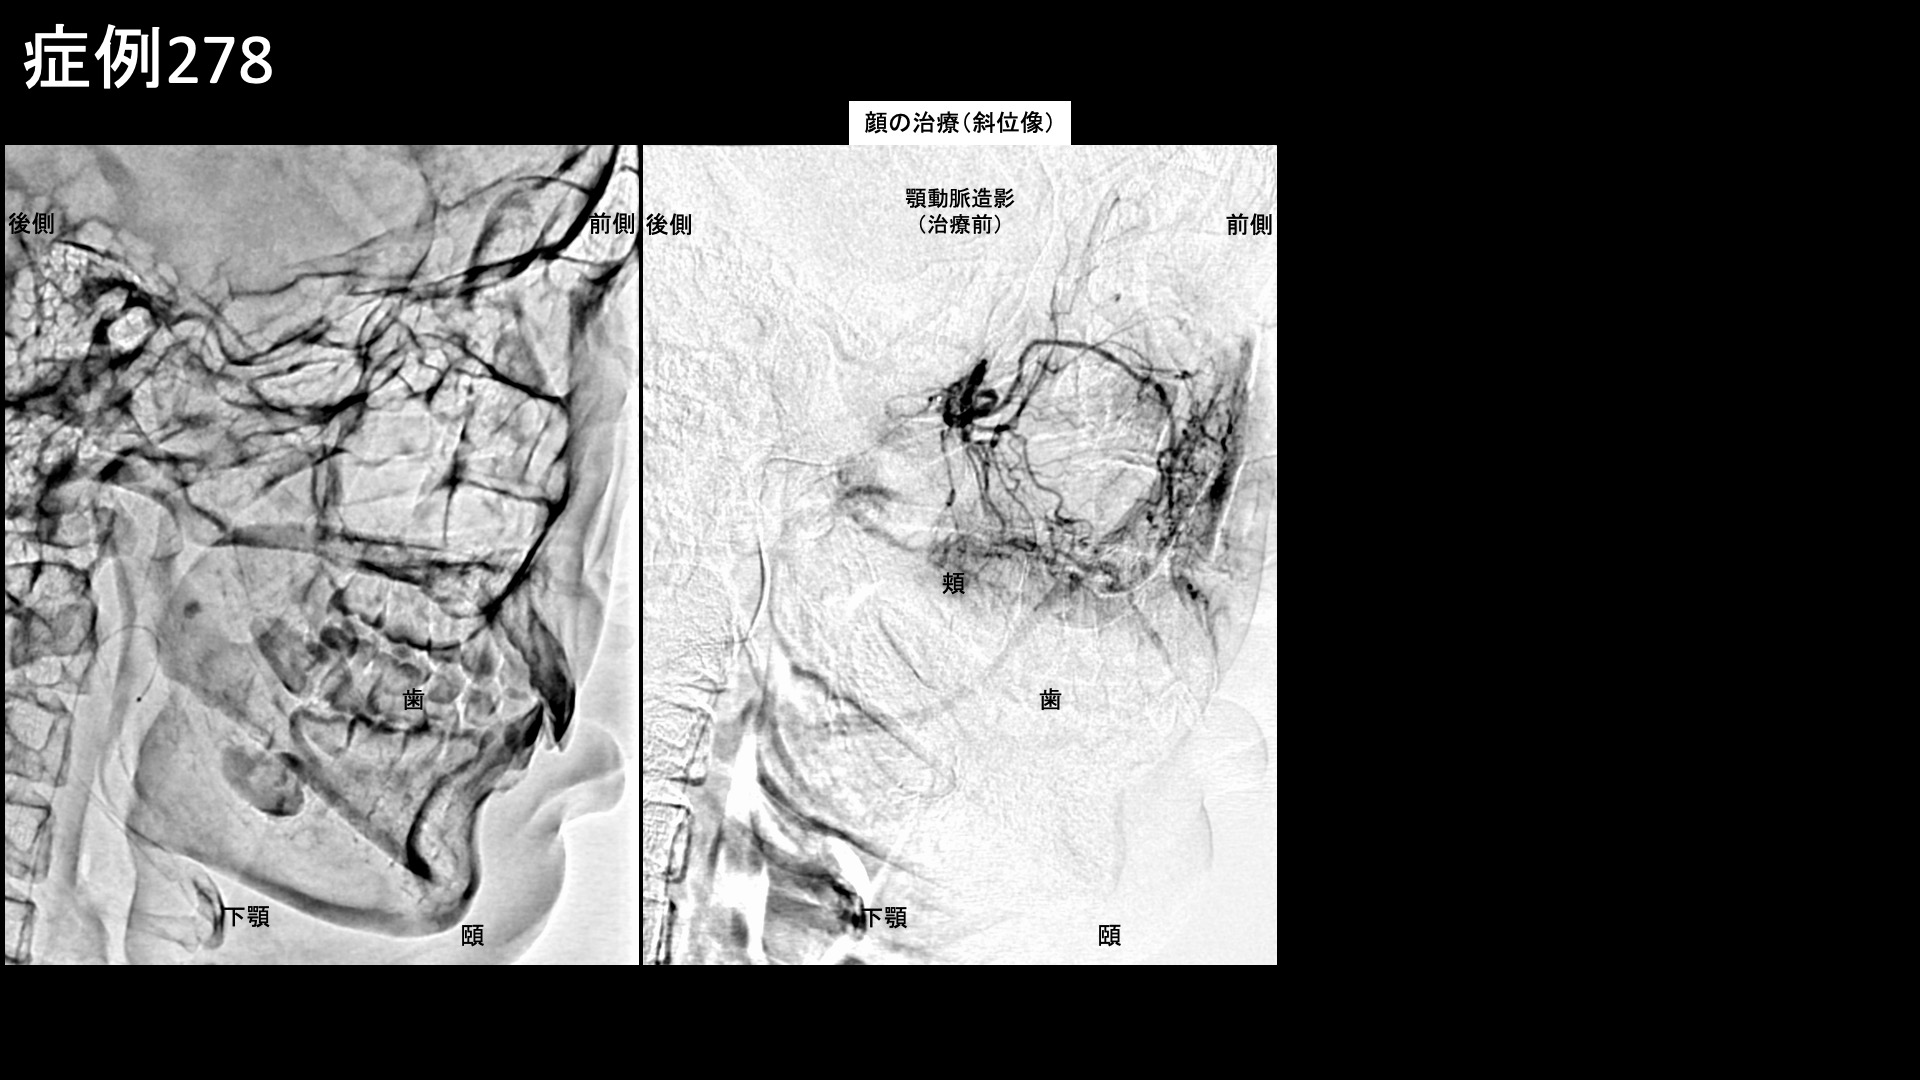

血管造影を行うと、頬や鼻に灌流する顎動脈、顎や口の周りに灌流する顔面動脈、額に灌流する浅側頭動脈でそれぞれモヤモヤ血管が濃染像として描出されました。治療後は画像上速やかに消失しました。その他複数箇所の治療を行い終了しました。

治療前画像:損傷を受ける、あるいは繰り返しのストレスにより発生した異常な新生血管

治療後画像:カテーテルを用いて塞栓物質を血管内に投与し新生血管を塞いだ状態